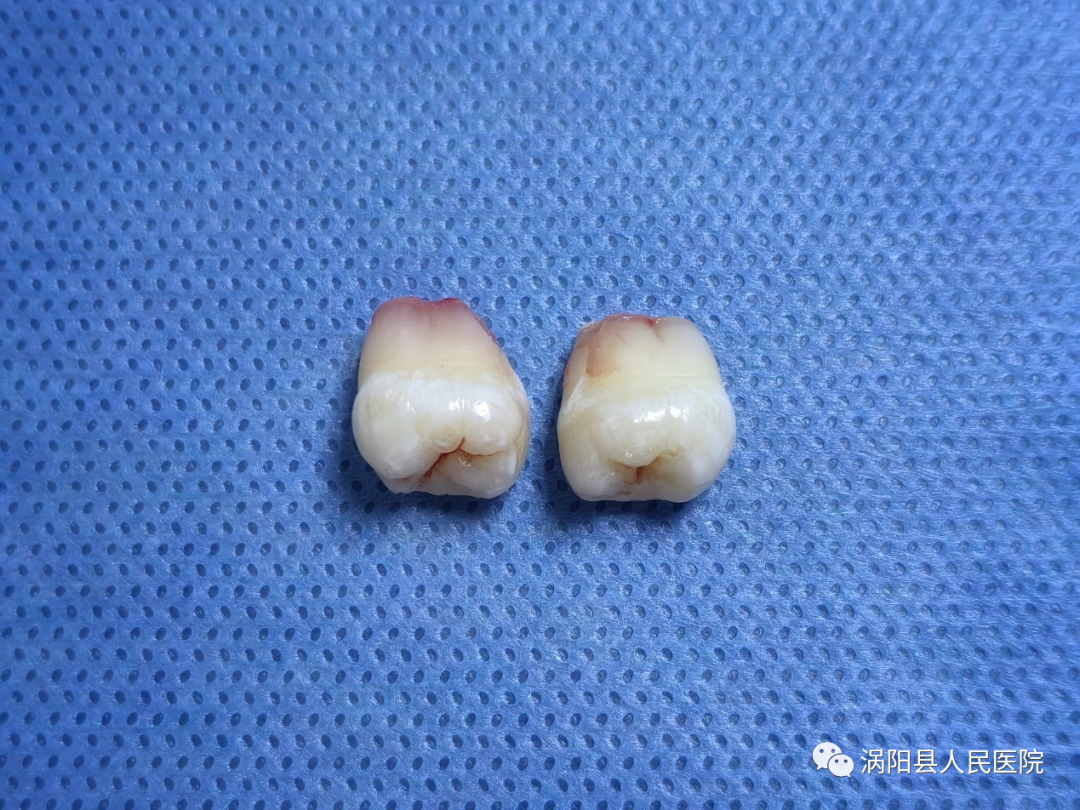

(拔除后的上下第三磨牙)

拔除后复查牙片可见周围骨质损伤较小,上颌结节完好。

拔除后的上颌双侧第三磨牙